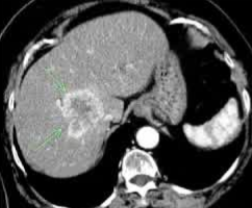

· 单中心、样本量小; 83 岁的女性,体重超标 40 毫米单发 ICC(S7-S8) 中肝静脉和右肝静脉浸润性,活检:非酒精性脂肪性肝炎(慢性肝病),马斯氏(MaS)病(30%)

考虑采用“三步策略 TARE→ PVE → Surgery”方案 剂量活性:1.56 和 3.16 GBq